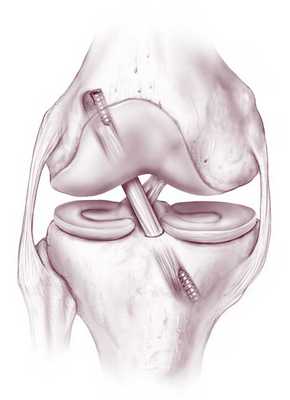

Операция на ПКС: виды пластики, принцип выполнения

Любая пластическая процедура на ПКС в настоящий момент выполняется методом малоинвазивной артроскопии. Артроскопический сеанс проходит закрытым способом под спинномозговой анестезией. Операция относится к щадящему типу хирургии высокой точности, поэтому мягким тканям, нервным и сосудистым образованиям не причиняется ущерб. Кроме того, манипуляции проводятся сугубо на пострадавшем участке, а после вмешательства никаких рубцов и шрамов не остается.

Чтобы осуществить реконструкцию поврежденного элемента, достаточно сделать один 5-мм прокол для оптического зонда, в который встроена миниатюрная видеокамера, и 1-2 дополнительных доступа (не более 8 мм в диаметре). Через вспомогательные отверстия хирург микрохирургическими инструментами будет заниматься воссозданием испорченной области. Зрительный контроль обеспечивает артроскоп (эндоскопический зонд), который выводит изображение оперируемой зоны на монитор в 40-60-кратном увеличении. Оперативное вмешательство может быть выполнено несколькими способами, рассмотрим их дальше.

В данном случае пересаживается фрагмент сухожилий пациента, взятый из мышц бедра, иногда берут материал из связок или сухожилий надколенника. На функциональности донорского участка это никак не отражается. Техника выполнения реконструкции заключается в удалении разорванных связочных структур с последующим внедрением на их место подготовленного трансплантата из сухожилий.

Зона «забора» материала.

Концевые участки сухожильного лоскута вдеваются в просверленные каналы бедренной и большеберцовой кости и натягиваются до нужных параметров, после чего закрепляются биоразлагаемыми винтами либо садятся на специальные петли. Через несколько месяцев без проблем происходит их полное врастание в кость. Методика хорошо изучена и имеет внушительную доказательную базу эффективности, поэтому является на сегодняшний день самой применяемой тактикой лечения ПКС, «золотым стандартом» ортопедии и травматологии.